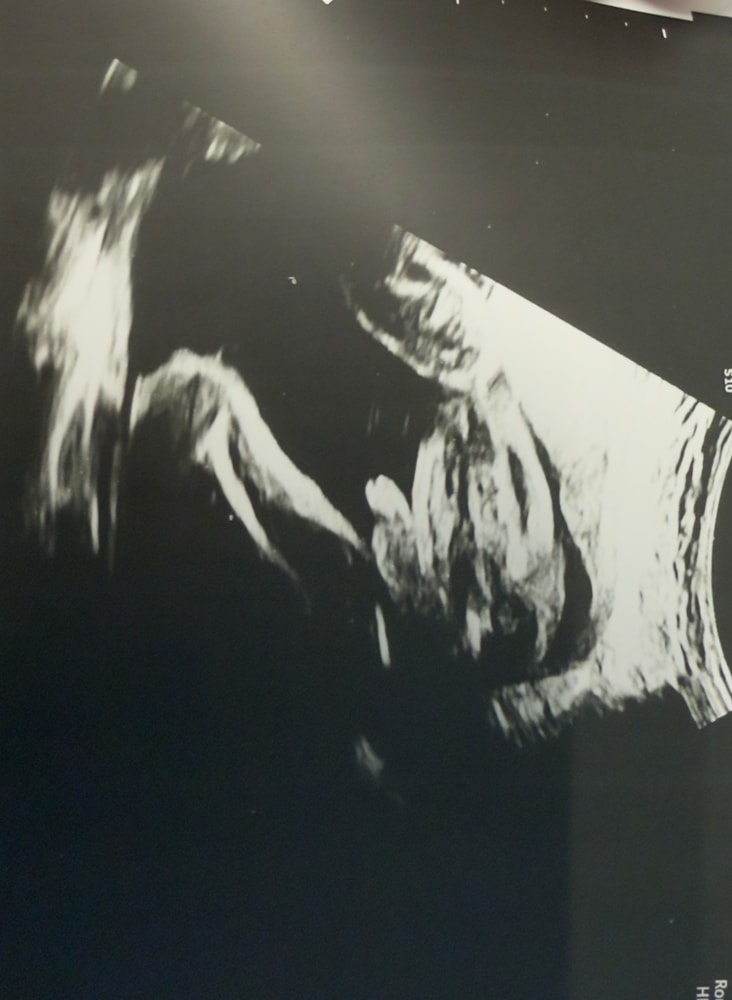

УЗИ мальчик в 23,6 недель

Если кто-то будет искать как выглядят узи мальчик/девочка ☺️